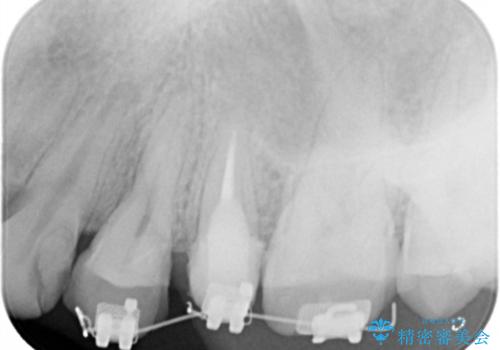

- 矯正装置

- 部分ワイヤー矯正

当初、歯ぐきよりも深い虫歯のぞんざいや、歯のポジションに問題がありましたがマルチブラケットを用いた部分矯正を行うことで適切な位置へと歯を移動させ、歯周環境を整えたセラミック治療を行うことができました。